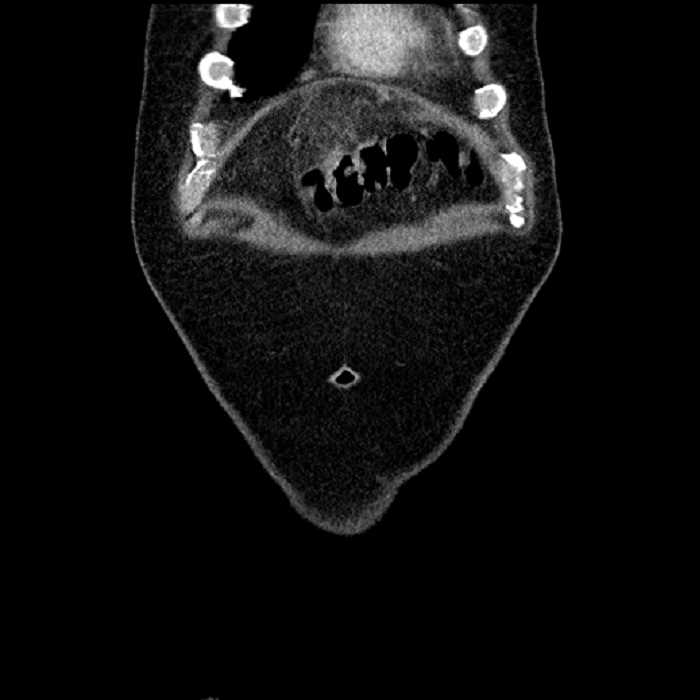

Age: 63

Sex: Male

Indication: Abdominal pain

• Mild mural thickening of a segment of the sigmoid colon with adjacent fat stranding and a 1.5 cm fluid and gas collection along the tip of an inflamed diverticulum

• Loss of the normal fat plane between this collection and adjacent loops of small bowel, which demonstrate mural thickening

Acute sigmoid diverticulitis complicated by a small contained perforation and a large abscess in the right hepatic lobe. Additional small subcapsular abscesses along the anterior margin of the left hepatic lobe.

Additionally, loss of the normal fat plane between the peridiverticular collection and adjacent thickened loops of small bowel raises the potential for an enterocolonic fistula.

Hepatic abscess showing the double target sign with low density internally surrounded by a thin inner enhancing rim (red arrow) and ill-defined outer low density rim (yellow arrow). Blue arrow indicates an internal septation. Red arrows: additional smaller subcapsular abscesses. Red arrow: focal contained perforation associated with diverticulitis.